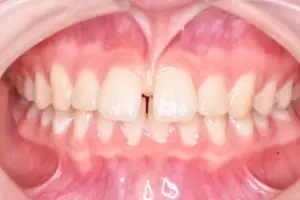

大人の矯正

「誰もが本当に喜べる矯正を提供したい」という治療目標を掲げる当院では、その実現のため、単に綺麗な歯並びに整えるだけでなく、原因の部分をきちんと治して、矯正後の咬み合わせの違和感や体調の変化を最小限に抑える治療を行なっています。

その結果として、治療期間の短縮や後戻り予防、たくさんの患者様からの喜びのお声につながっています。